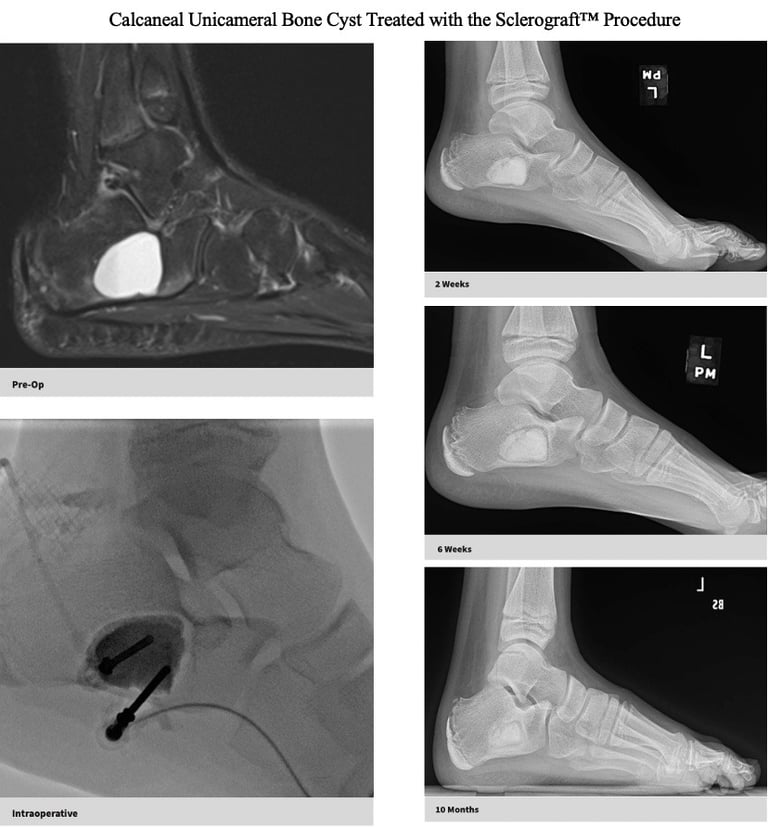

Gallery

Explore our educational resources and images